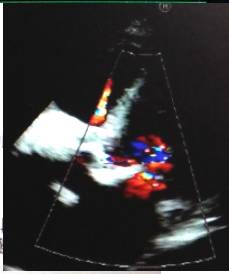

心脏彩超

●全心增大,左室壁增厚。

●主动脉瓣钙化,狭窄(中-重度)并关闭不全(轻度)。

●三尖瓣大量返流,肺动脉高压(中度)。

●左心功能减低。

●心包腔少量积液。

●左侧胸腔积液。